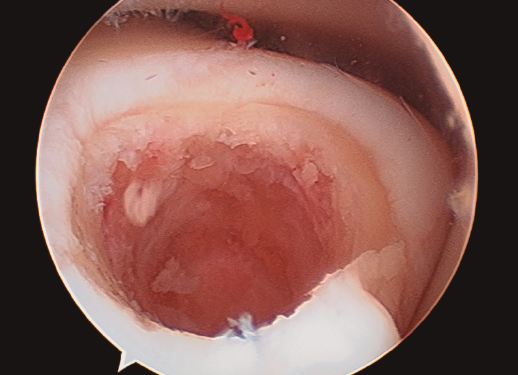

Figura 3. Secado de la articulación con aspirador.

- Una vez se completa el desbridamiento de la capa mineralizada, detenemos la infusión de suero salino y procedemos al secado meticuloso de la misma mediante aspiración y empleo de gasas y torundas (Figura 3).